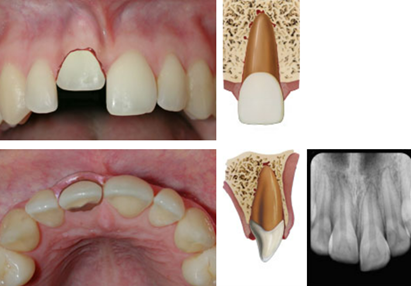

dx intrusion

A

Tooth displaced axially into alveolar bone

High metallic/ankylotic sound

Mobile

Negative sensibility tests

Occlusal, PA and 2 eccentric horizontal angulations

* PDL space may be absent from all or part of the root

* ACJ located more apically in the intruded tooth than in adjacent non-injured teeth, at times even apical to marginal bone level